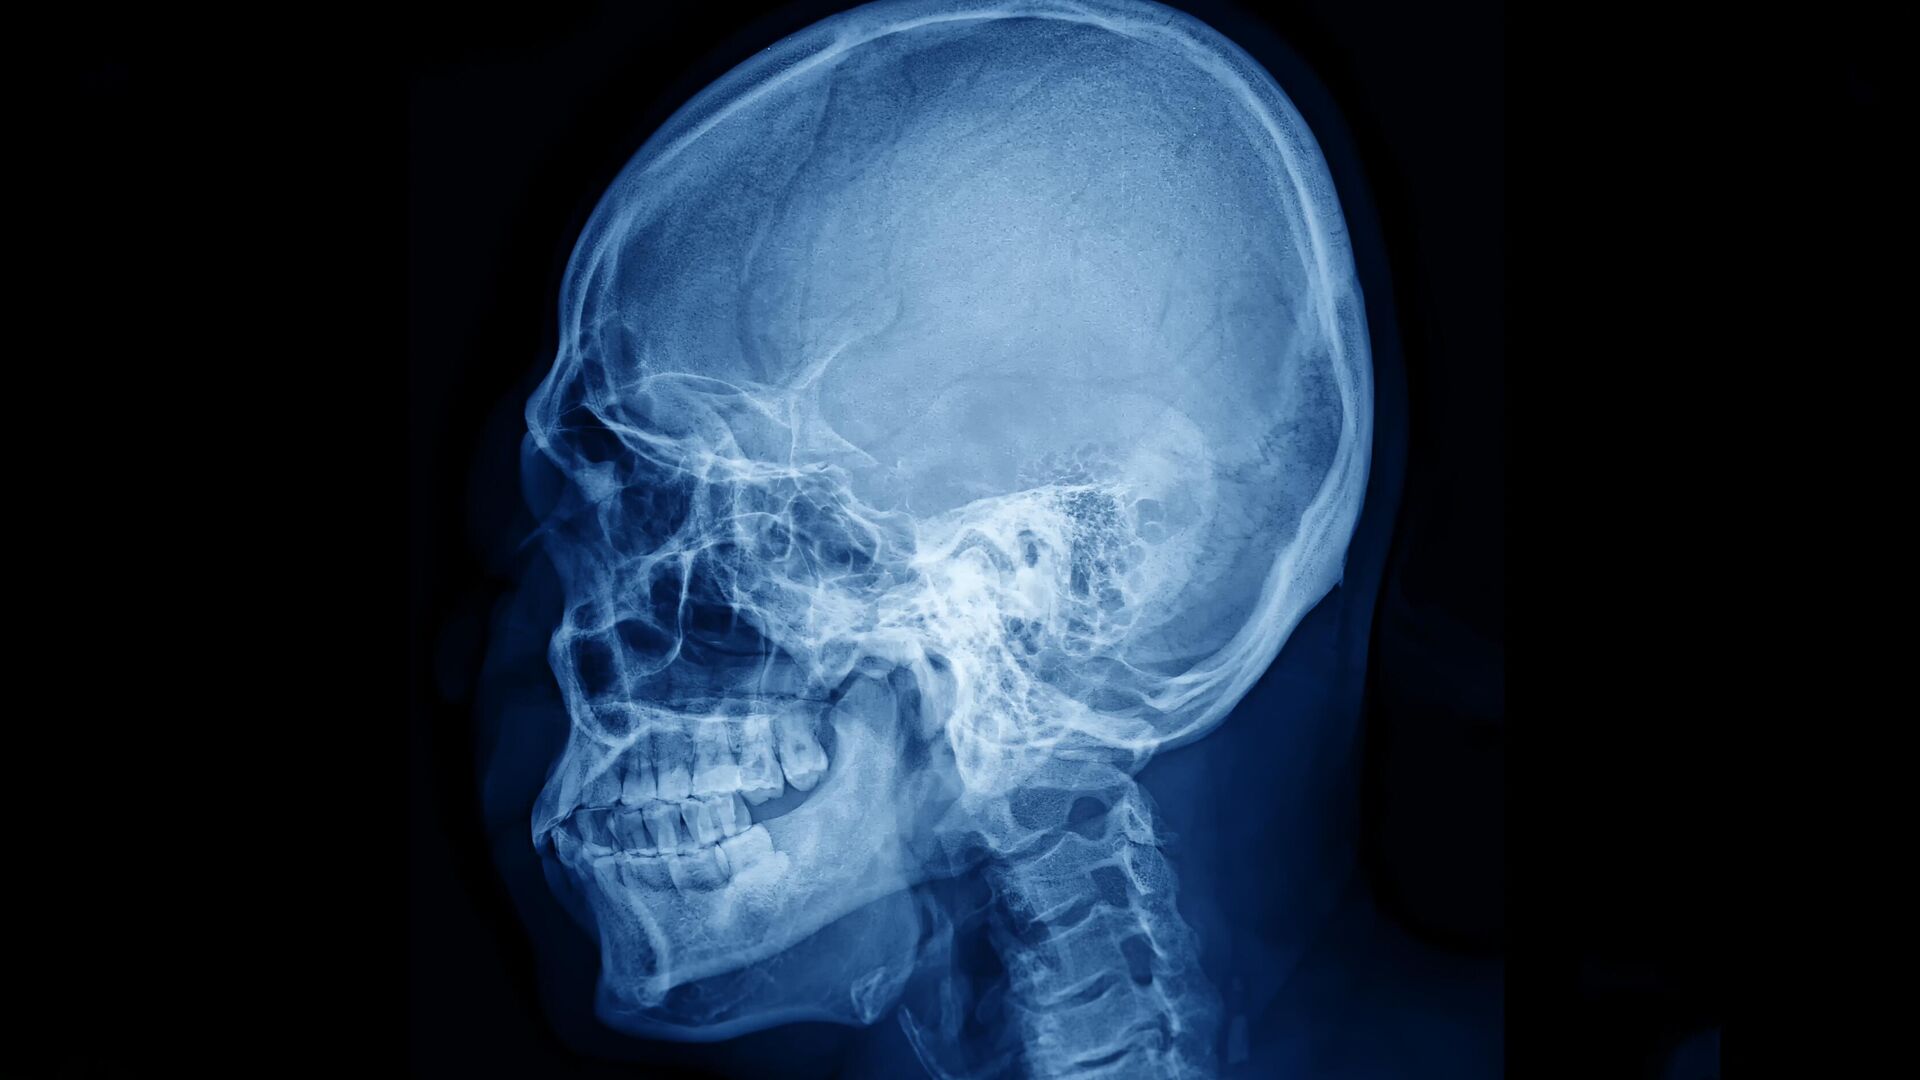

В настоящее время для того, чтобы увидеть сосуды мозга с хорошим качеством, часто приходится истончать кость или делать отверстие в черепе, поскольку костный материал сильно рассеивает лазерный свет и «смазывает» изображение. Именно лазерный свет используется в одном из распространенных методов наблюдения за кровотоком в головном мозге — лазерной спекл-контрастной визуализации, рассказал младший научный сотрудник лаборатории биомедицинской фотоакустики СГУ Юрий Сурков. Из-за рассеяния в кости получаются искаженные карты сосудов и перфузии головного мозга, добавил ученый.

Исследователи СГУ совместно с коллегами из Сеченовского университета, НМИЦ нейрохирургии имени Н. Н. Бурденко, НИУ МИЭТ и Университета Астон (Бирмингем, Великобритания) предложили способ примерно на 100 процентов увеличить контрастность карт сосудов, полученных при наблюдении мозгового кровотока через целый череп. Сосуды стали видны четче, а часть сосудистой сети, которая раньше терялась на фоне кости, проявилась и стала различимой.